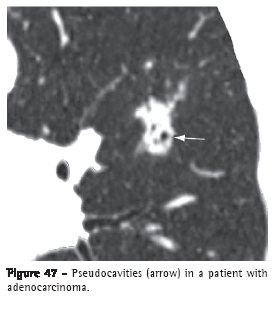

Pseudocavity (pseudocavidade)A pseudocavity is a round or oval-shaped area of low attenuation in nodules, pulmonary masses or areas of consolidation within a portion of preserved pulmonary parenchyma, within dilated or normal bronchi or (as an area of emphysema) within a lesion (Figure 47). Pseudocavities generally measure less than 1 cm in diameter. They can be seen in patients with adenocarcinoma, bronchioloalveolar carcinoma or pneumonia.(7,72)